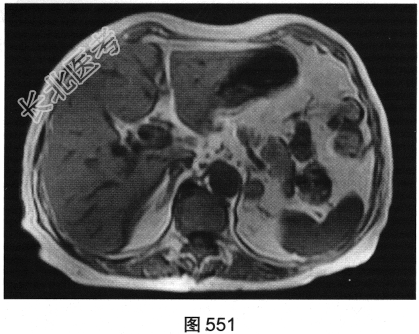

- 多项选择题3.[提示]MRI平扫+增强(图550~图555):T1WI正相位, 左侧肾上腺外侧肢可见类圆形T1WI稍高信号结节。T1WI反相位,结节信号明显减低。T2WI脂肪抑制, 结节呈均匀低信号。动态增强,动脉期结节轻度均匀强化, 静脉期结节呈相对低信号,延迟期结节呈相对低信号。可考虑的鉴别诊断为( )